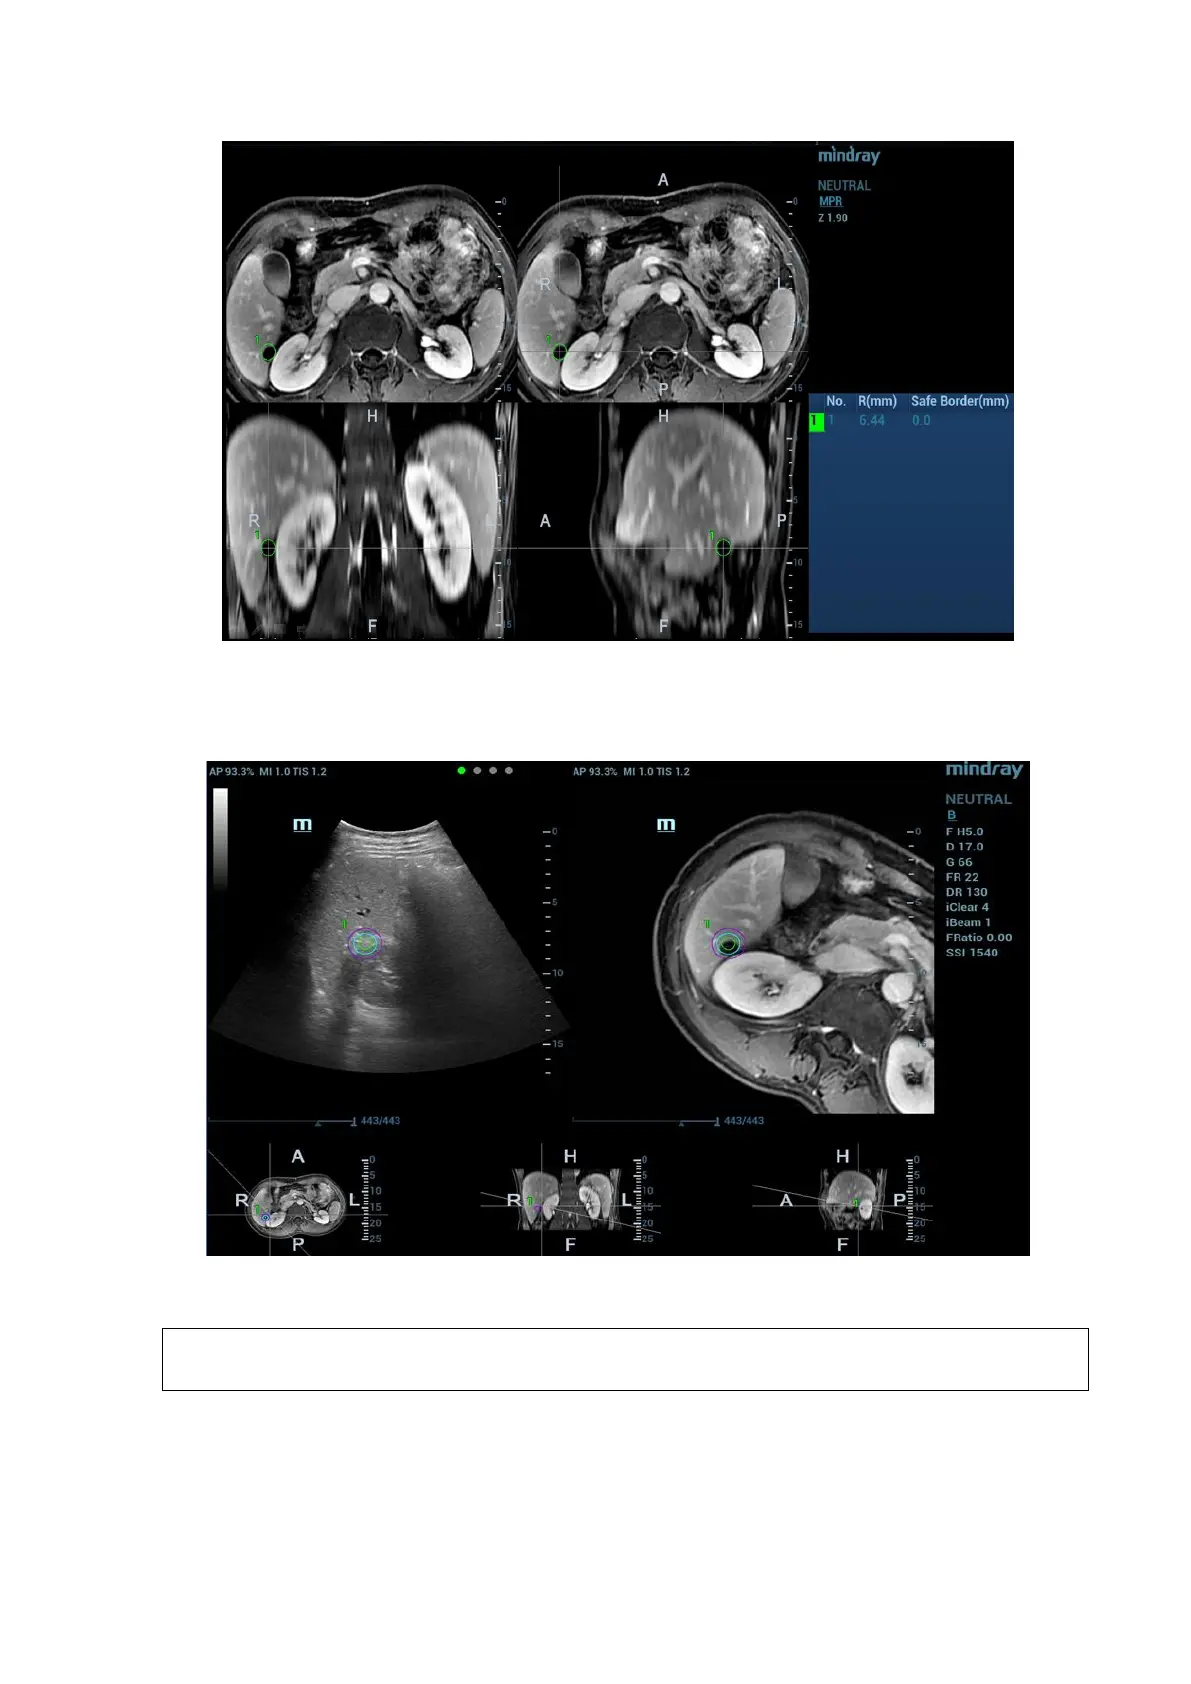

The mark in the following figure is enveloped with three circles. There are real-time tumor,

mark tumor (completed in step 3), and ablative margin from inside to outside.